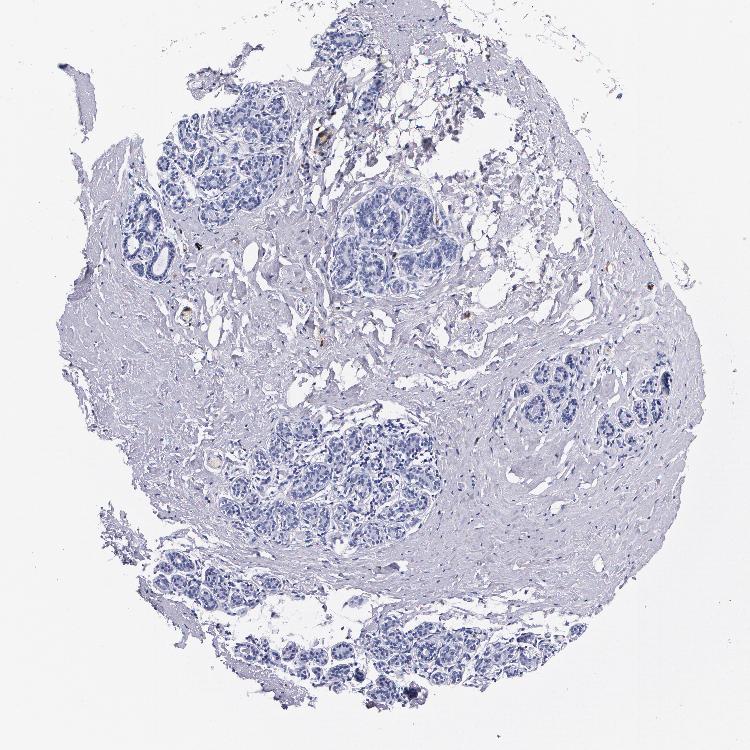

BREAST - Antibody stainingi

Antibody staining in the annotated cell types in the current human tissue is reported as not detected, low, medium, or high, based on conventional immunohistochemistry profiling in selected tissues. This score is based on the combination of the staining intensity and fraction of stained cells.

Each image is clickable and will lead to virtual microscopy that enables deeper exploration of all samples and also displays staining intensity scores, fraction scores and subcellular localization as well as patient and tissue information for each sample.

Antibody HPA024372Antibody CAB002791

Adipocytes Not detectedNot detected

Glandular cells Not detectedNot detected

Myoepithelial cells Not detectedNot detected